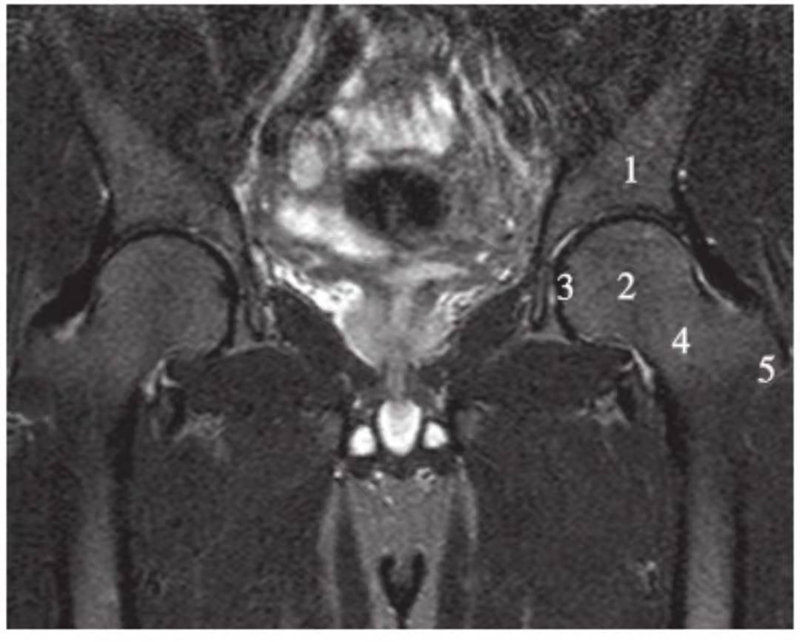

正常髋关节经股骨头中心层面T1WI像

1.股骨头;2.股骨颈;3.髋臼窝内脂肪;4.髂骨;5.臀小肌;6.臀中肌;7.闭孔内肌;8.闭孔外肌;9.股外侧肌;10.股内侧肌